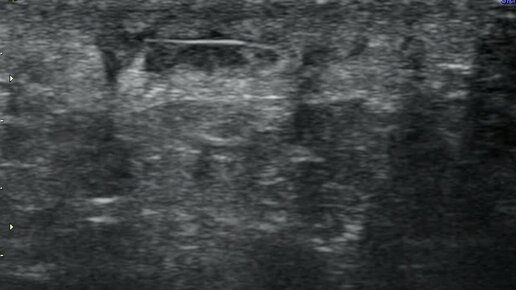

Инородное тело (заноза) в мягких тканях ягодичной области

Ультразвуковые находки от врача УЗД Зорина Я.П.